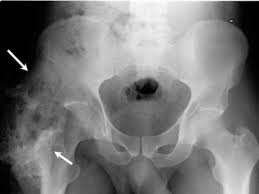

Radiografia este specifica in diagnosticul osificarii heterotopice, dar nu este sensibila in diagnosticul precoce. Deoarece calcificarile tesutului moale sunt detectate de radiografie doar la maturitate metabolica. Studiul identifica leziunile ca pete care fuzioneaza si se maresc la examinarile ulterioare, iar in 3 luni se identifica osul matur. Este nevoie de 2 saptamani inainte de mineralizarea suficienta a leziunilor pentru a fi detectabile pe radiografie.